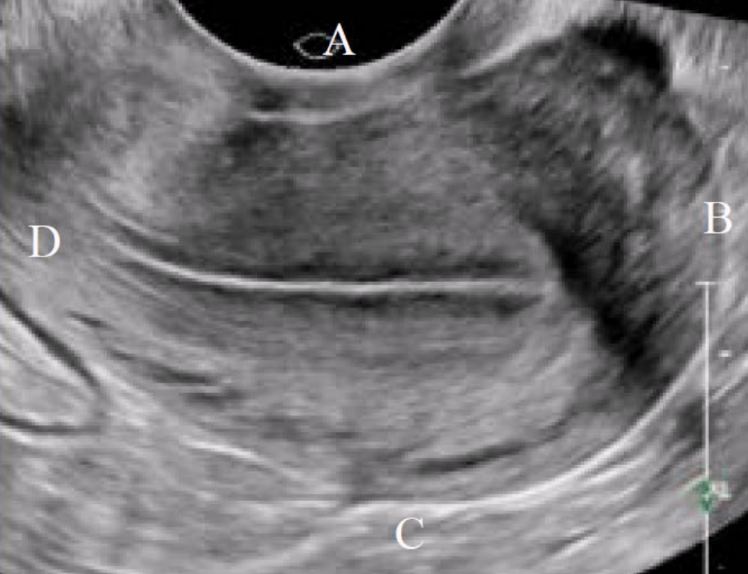

What is letter C in this image?

a. Left

b. Posterior

c. Inferior

d. Superior

Inferior

What is letter B in this image?

a. Posterior

b. Left

Posterior

What type of fibroid is depicted in this image?

A. Intramural

B. Submucosal

C. Subserosal

D. Pedunculated

Intramural